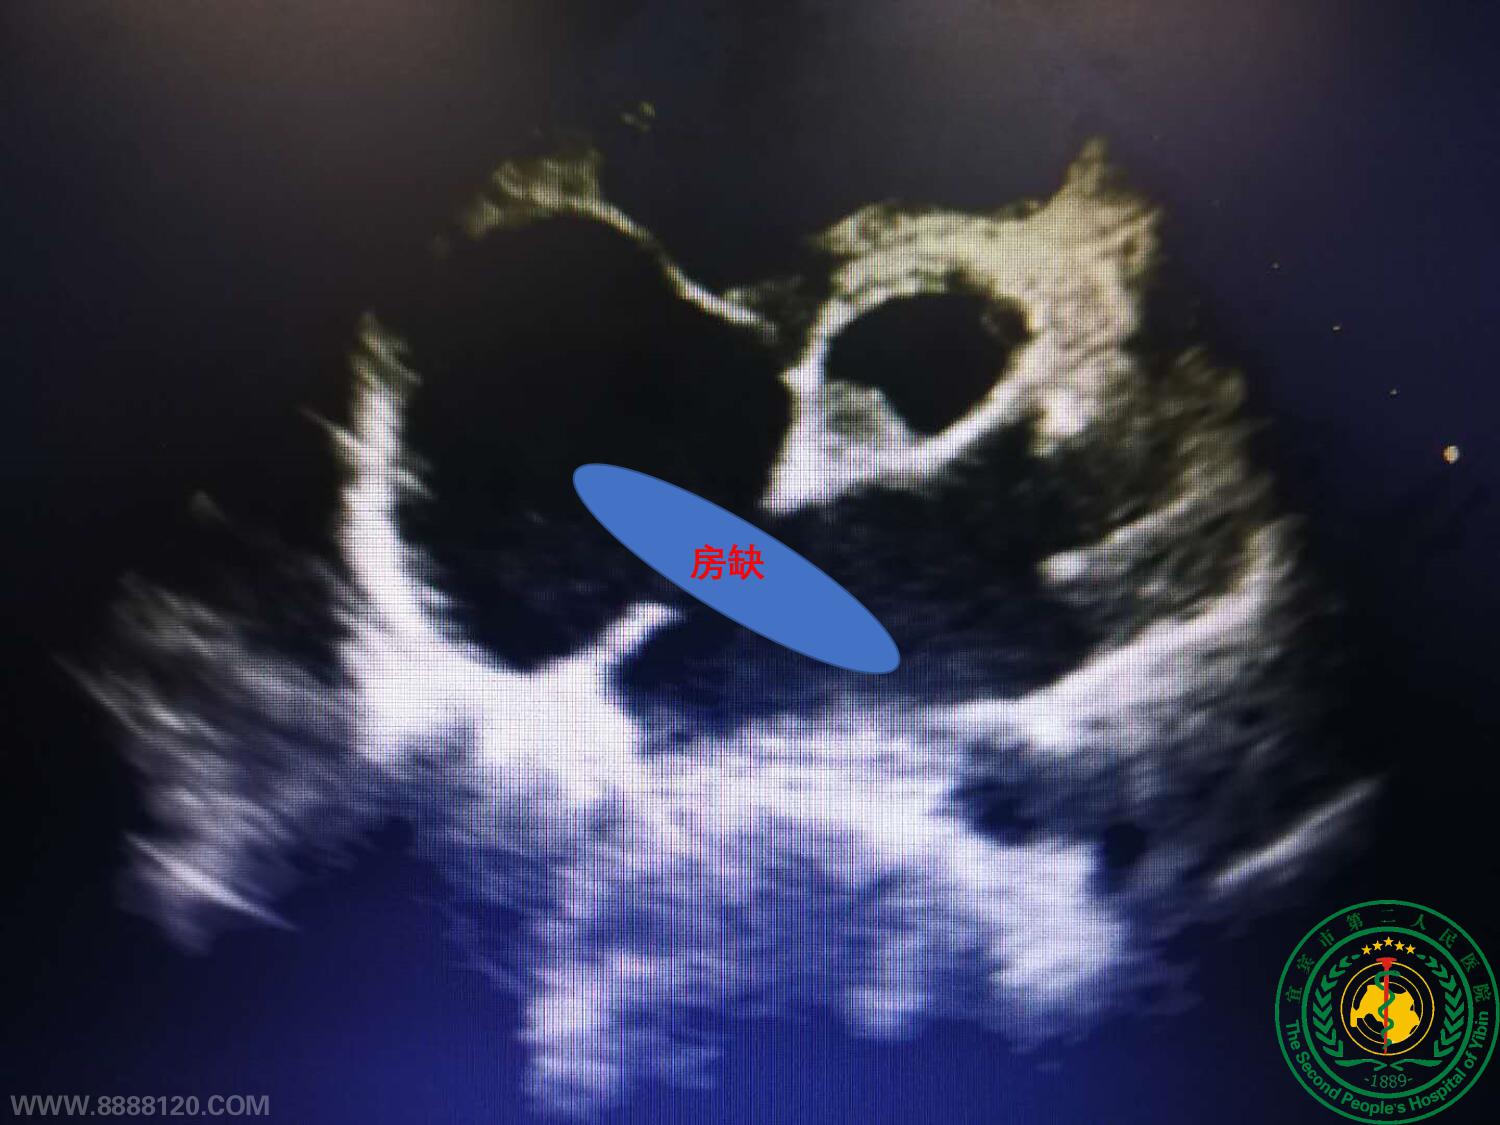

我院成功开展宜宾首例超声引导经胸房缺封堵术

我院成功开展宜宾首例超声引导经胸房缺封堵术16909